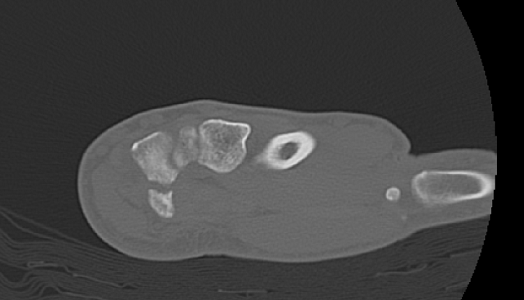

An 80 year old female presents to your office with a left ring finger deformity after a fall one week ago. She initially went to urgent care and xrays were unremarkable for a fracture (Figures 1 and 2). A photo of her left ring finger is shown in figure 3. On physical exam the left ring finger is in hyperextension at the PIP joint and flexion at the DIP joint. She able to flex her PIP joint with full motion. What is the best treatment option?